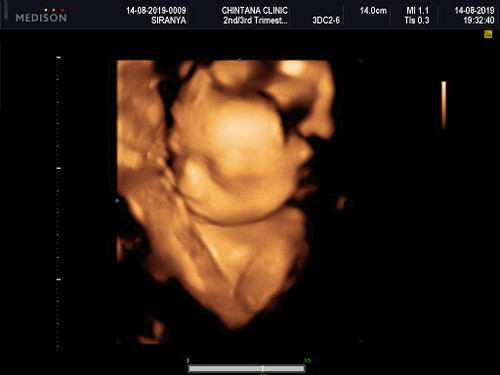

บ้านนี้ได้เห็นหน้าลูกครั้งแรก ชื่นใจมาเลยค่ะ เมื่อ 10 วันที่ผ่านมา เป็นการนัดซาวด์เพศ ก็ไม้เห็นเพศค่ะ แต่น้องไม่ยอมให้ดูหน้า เอามือปิดหน้า บังหน้าตลอด จนวันนี้ได้กลับไปซาวด์ซ้ำ ช่วงแรกๆ มีบิดตัวหนีค่ะ เอามือบังบ้าง จนคุณหมอบอกว่า "แอบเก่งจริงๆ" แม่บ้านนี้ได้ลูกชายสมใจเลยค่ะ 10 วันที่แล้ว น้ำหนักลูก 691 กรัม วันนี้ได้ 964 กรัม ขึ้นไวจนคุณหมอยังตกใจ แต่ดีนะคะน้ำหนักแม่ไม่ขึ้น ตอนนี้ 25 +6 วีคแล้วค่ะ แม่ๆบ้านอื่นเป็นยังไงกันบ้างคะ

โนอาห์ลูกรัก